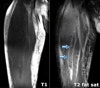

MRI : 대퇴부 염좌(Hamstring tendinosis)

T1 : Hypointense tendon, T2 : Proximal hyperintensity